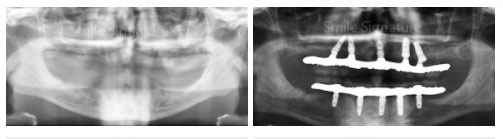

1. BEFORE THE PROCEDURE

During your first visit, your dentist asks about your concerns and discuss your treatment options for missing teeth restorations. A panoramic x-ray and/or CT Scan is taken. Using the x-ray imaging, your dentist confirms your treatment plan and informs you on other potential treatments required for a successful outcome. If you require temporary dentures to wear during the healing period back home after implant post placement, your dentist may take a tooth impression either prior to installing the implants or after the implant surgery depending on your dentures construct and dentist recommendations.

2. INSTALLING THE TOOTH IMPLANTS

The first step is installing tooth implants is embedded the implant posts into the jaw bone. In this illustration, 4 implants are placed into the jaw bone. After implant placements, your dentist makes a re-check appointment about 5 to 7 days later to re-check the implant wound healing.

3. ATTACHING THE OVERDENTURES

During your return visit, your dentist takes a panoramic x-ray to check if the implant posts is successfully integrated with the jaw bone. Your dentists takes tooth impressions to construct your permanent dentures in the dental labs. On its delivery, locators, balls or bars are screwed into the implant posts with the dentures snapped over securely over.